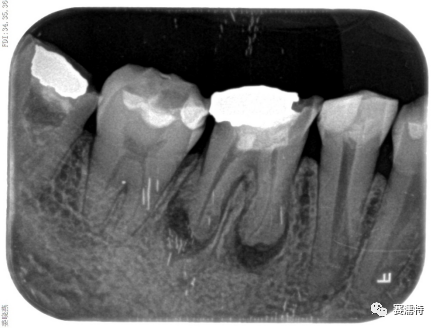

張云鳳老師案例